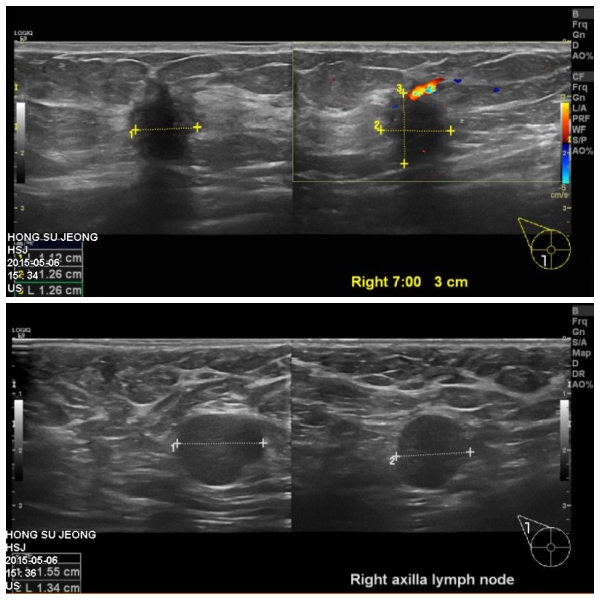

우측 유방에 만저지는 몽우리로 내원하신 50대 여성분으로 본원에서 만저지는

몽우리와 겨드랑이 조직검사 시행 하였으며, 우측 침윤성 유관암 진단 되었습니다.

또한 겨드랑이 전이로 나왔습니다.